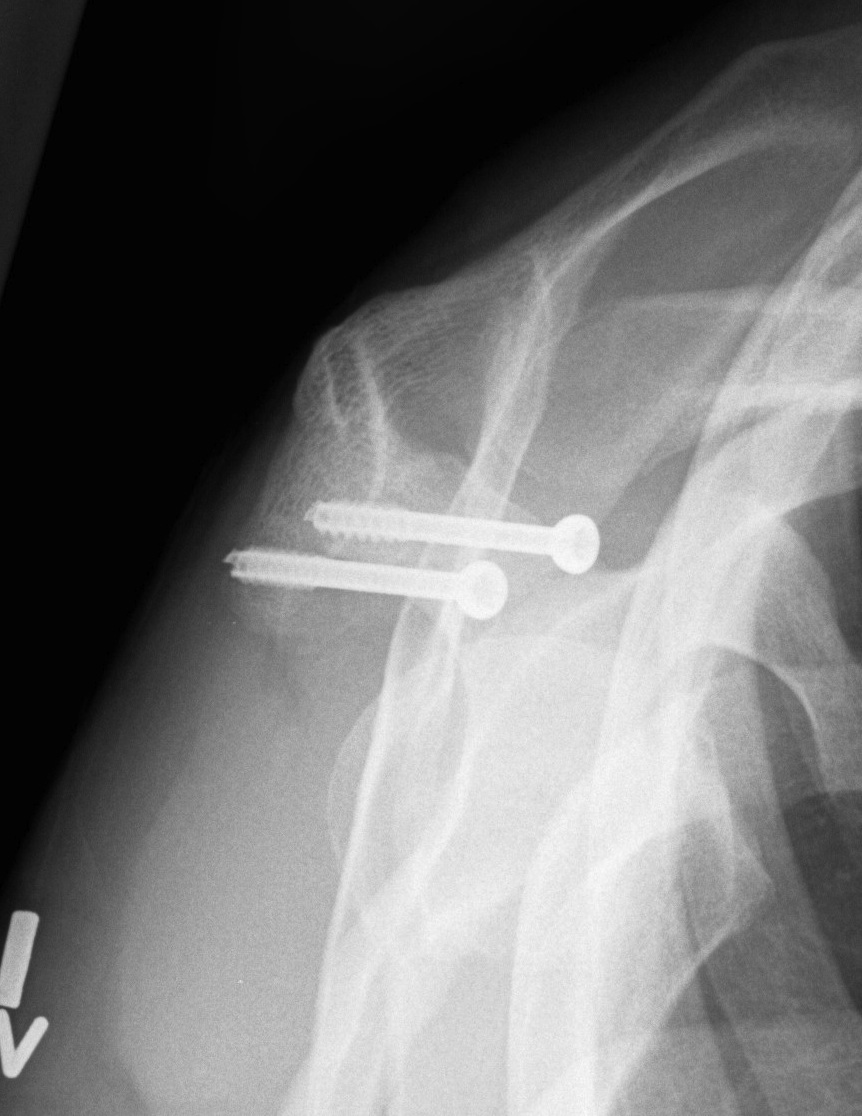

X-ray

Best seen on axillary lateral

Axillary lateral showing meso-acromion Scapula lateral xray showing os acromiale